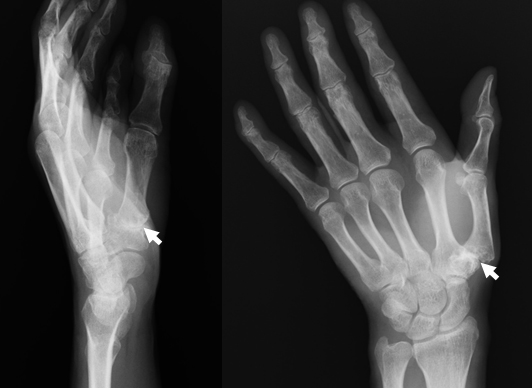

母指CM関節固定術は、軟骨が摩耗して痛みや変形が強い関節をプレートやスクリューで固定する手術です。

- 母指のジグザグ変形が著明

- 母指の付け根に痛みが強く摘むことが困難

- 母指の変形は矯正

- 母指の付け根の痛みは消失し摘む力も増加